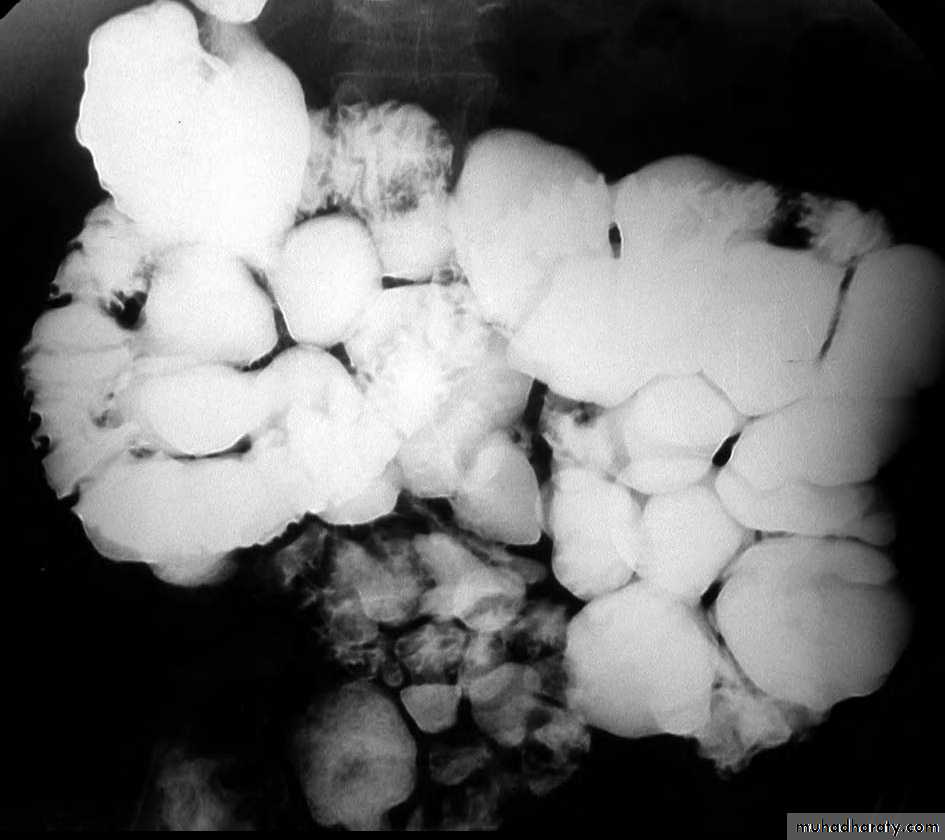

The central barium collections (ulcer crater) and mounds of edema are characteristic of aphthous ulcers.A cobblestone mucosal pattern affects a nonstenotic segment of small bowel

c. Due to bowel wall thickening, the folds may be thickened, distorted or disappear & the loops may be separated in severe wall thickening. With inflammatory mass, greater displacement of loops is seen.Mucosal fold thickening, ulceration, nodularity, asymmetric bowel wall

involvement, regions of narrowing, and separation of small bowel loops are present.d. Fistulae to the other loops of SB, colon, bladder or vagina.